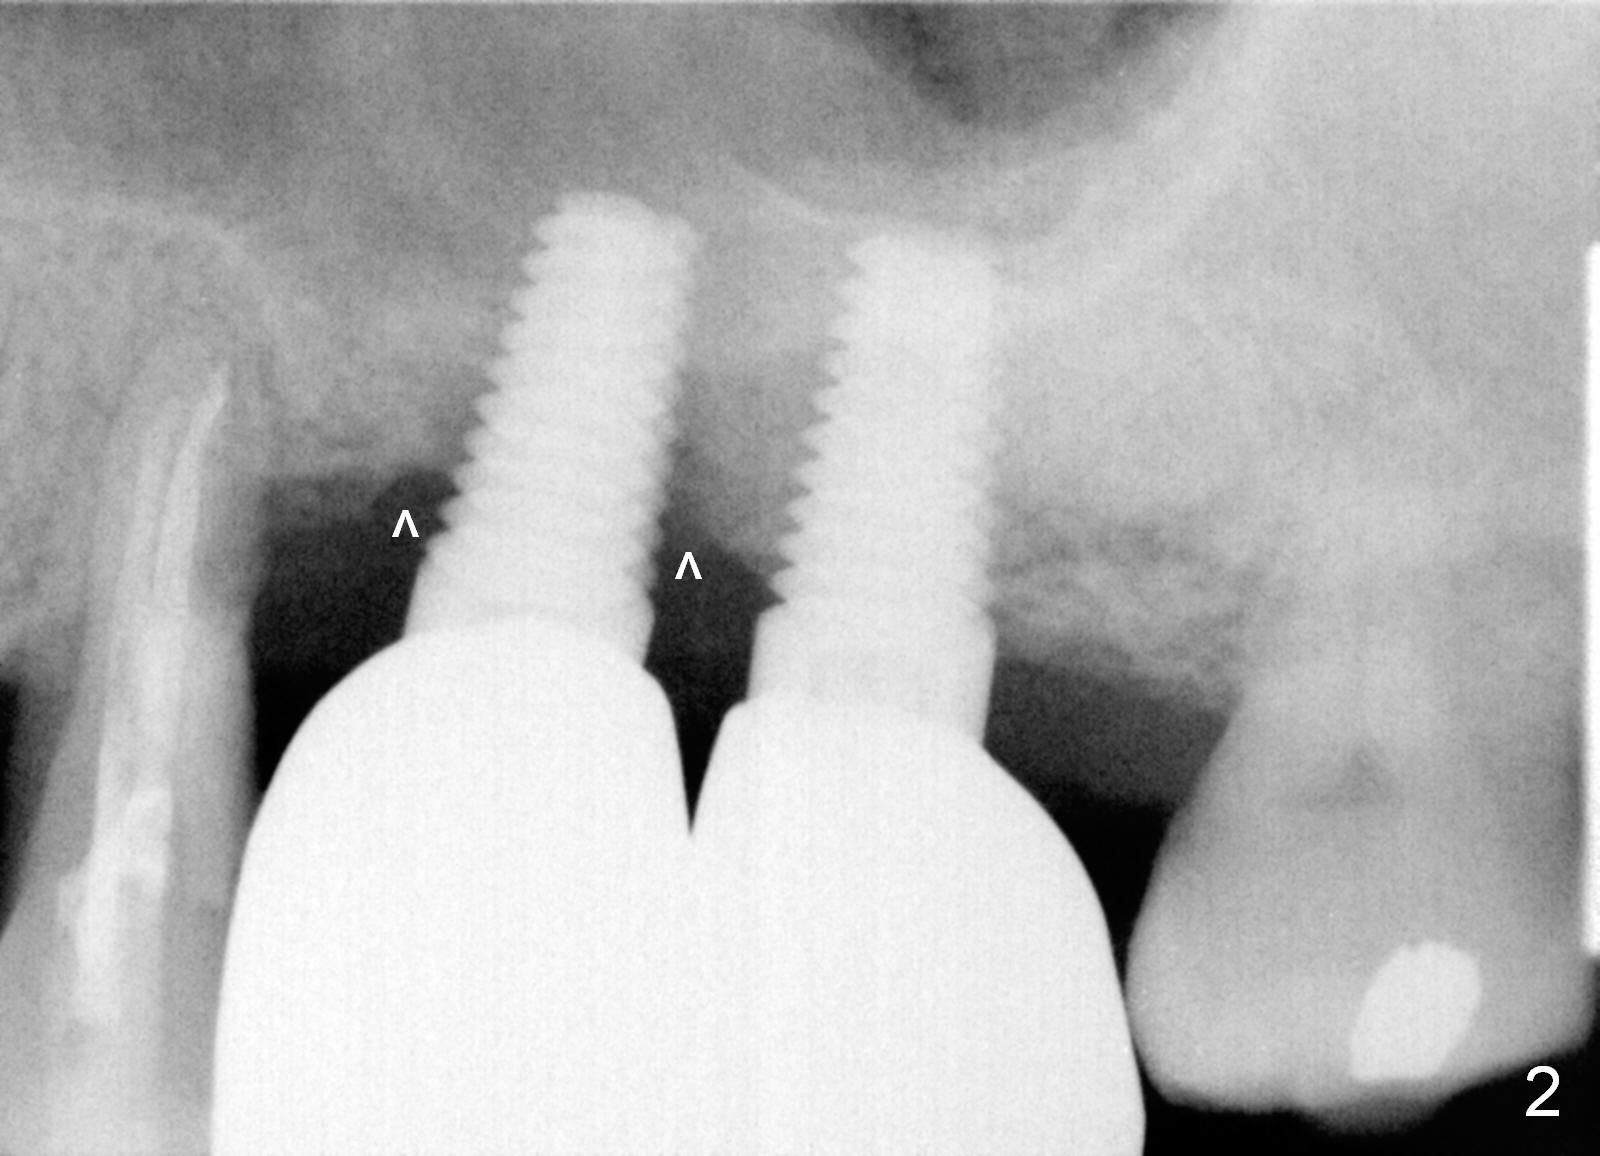

Three months post cementation, the crown at #14 is found to have mobility I with mild tenderness and bone loss (Fig.1,2 ^). The crown/implant ratio is unfavorable (Fig.1). The 1st option of treatment is to remove the crown and the unipost and place a healing screw if the gingiva is healthy. If the implant is fatally loose, remove it, explorer the osteotomy for wall integrity. If it is solid, place 5.5 or 6.0 mm tap (Fig.3) before placing an appropriate implant (e.g., 6x6 mm; allograft for internal sinus lift and coronally) and healing abutment for more than 6 months (vs. 4 months previously). When the implant seems to have osteointegrated, place a provisional from infraocclusion to ortho-occlusion over time (6 months, progressive loading). When the implant appears to withstand normal loading, fabricate a single-unit crown. If not, remove #15 crown and splint #14 and 15 crowns or #13 and 14 in case the tooth #13 fails (Fig.2 limited bone height).